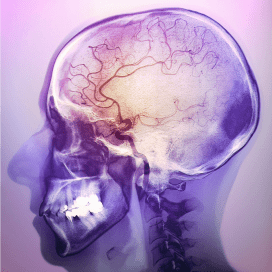

In tegenstelling tot wat internationale richtlijnen stellen, is preventief vocht toedienen om de nieren te beschermen bij contrastvloeistofonderzoek overbodig. Dat concluderen onderzoekers van Maastricht UMC op 20 februari in The Lancet.

Uit het onderzoek van het MUMC bleek dat het voor de nierfunctie geen verschil maakte of patiënten met verminderde nierfunctie vocht toegediend kregen voorafgaand aan onderzoek met contrastvloeistof (zoals een CT-scan). Wel ondervond een klein deel van de patiënten complicaties (waaronder hartklachten) door de vochttoediening.

Veilige toediening

In het MUMC-onderzoek bleek dat er uitsluitend een laag-toxische contrastvloeistof werd gebruikt. Het contrastmiddel werd altijd eerst voorverwarmd tot lichaamstemperatuur, en de hoeveelheid werd individueel aangepast. Dat deze manier van contrasttoediening effectief en veilig blijkt te zijn, ook voor patiënten met verminderde nierfunctie, is volgens Nijssen een van de belangrijkere boodschappen van haar onderzoek.

In twee jaar tijd deden 660 patiënten met een verminderde nierfunctie (eGFR < 59 ml/min.) mee aan de studie. Zij kwamen voor uiteenlopende onderzoeken met contrastvloeistof naar het ziekenhuis. Patiënten op de spoedeisende hulp en de intensive care werden niet meegenomen in het onderzoek. Ongeveer de helft kreeg intraveneus vocht toegediend, de andere helft niet. In beide groepen trad er bij ongeveer 2,5 procent van de patiënten een acute daling van de nierfunctie op.